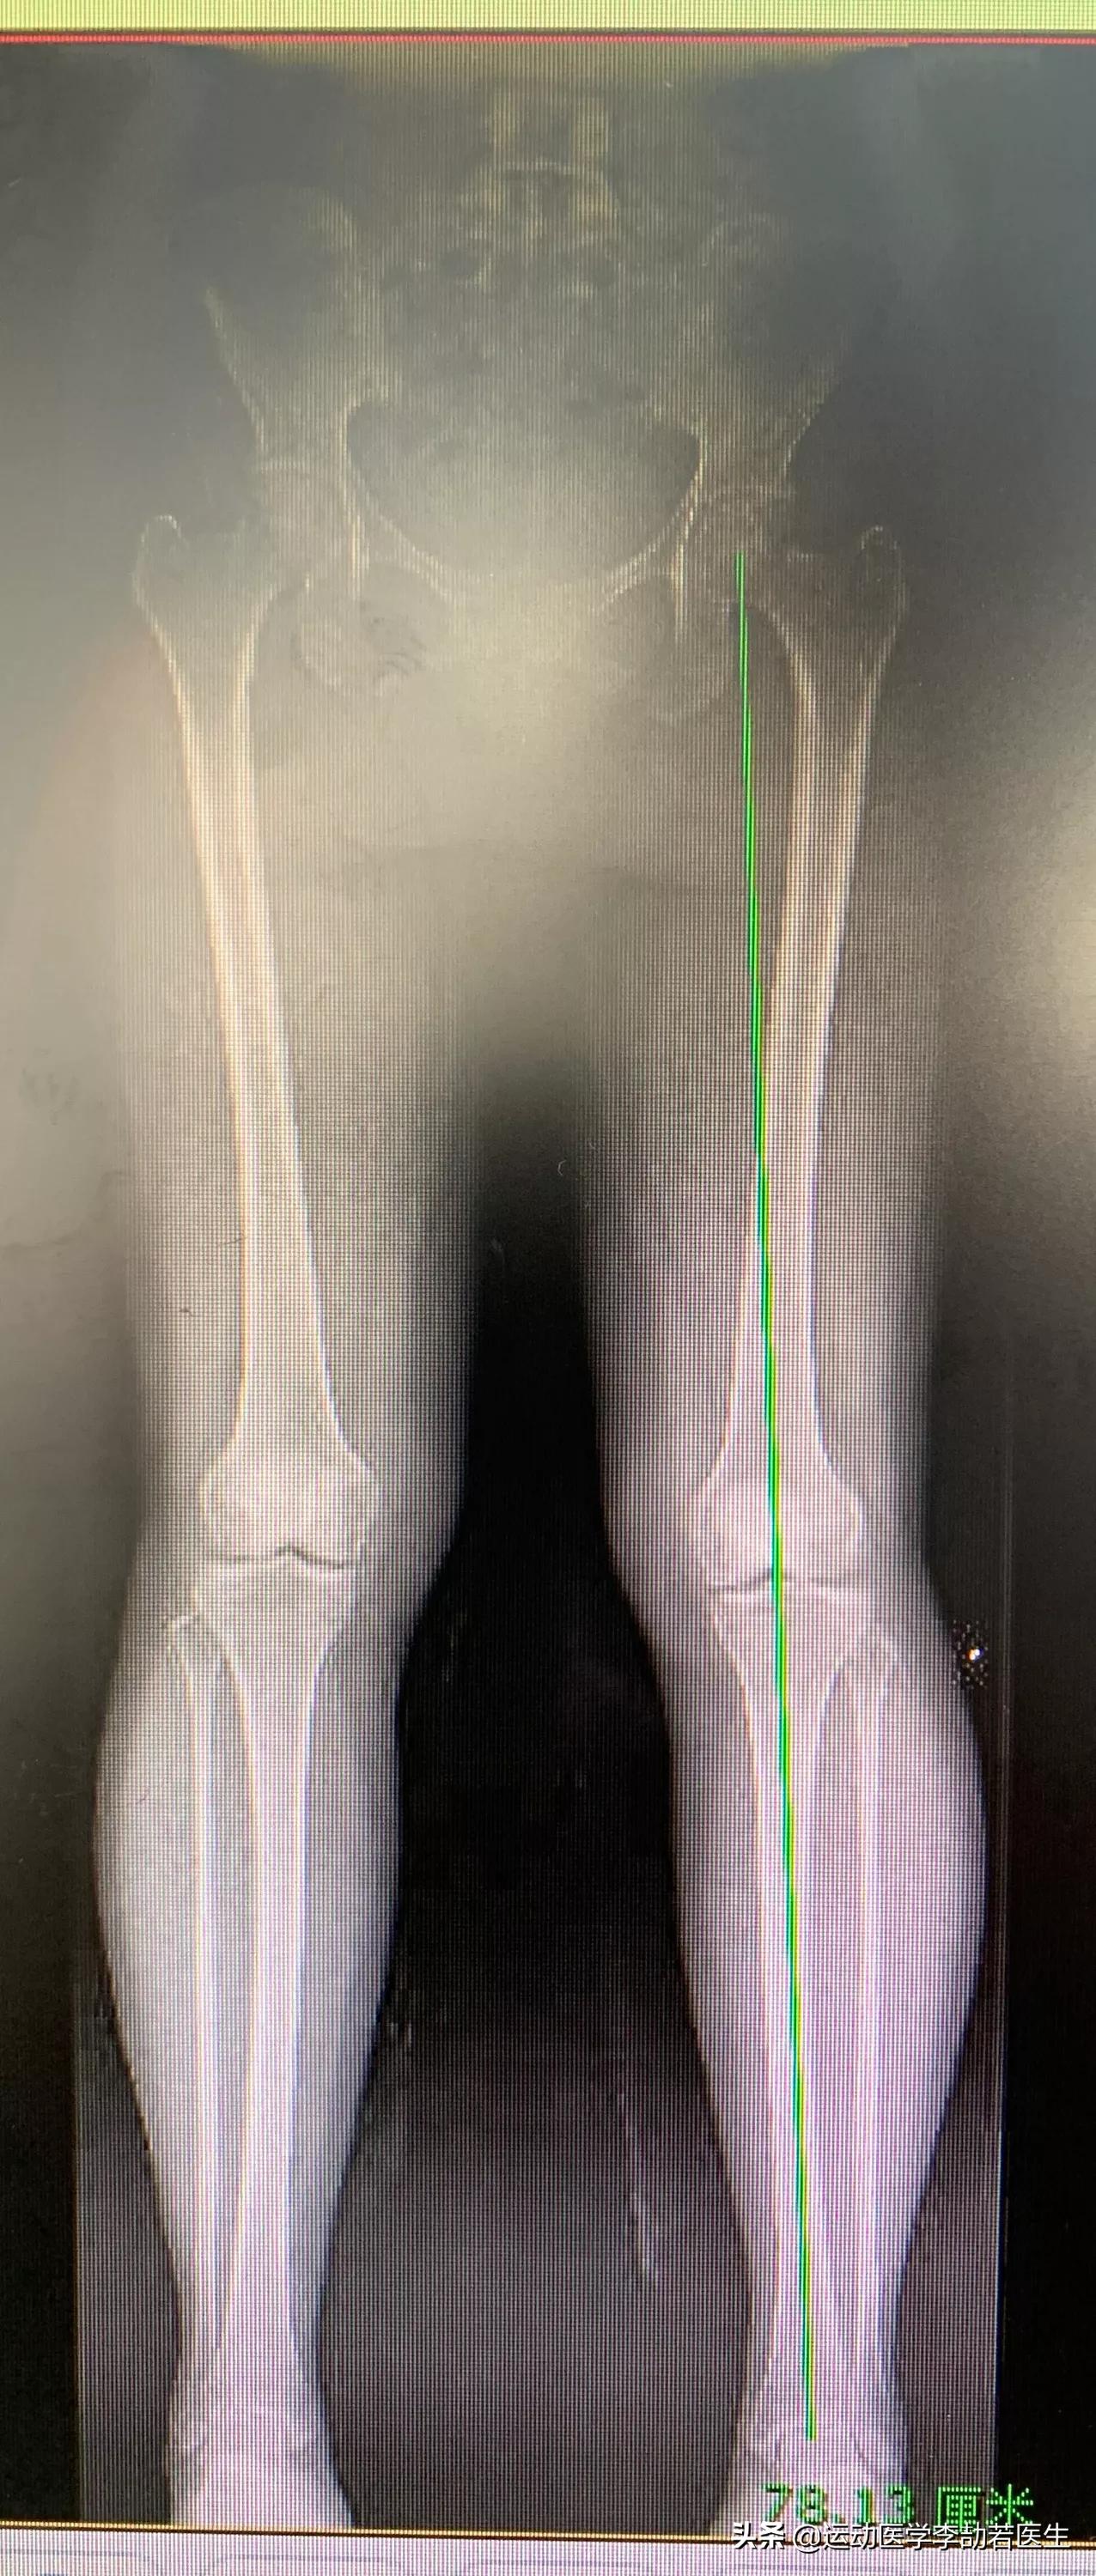

简单具体说,我们首先要看力线、关节间隙(图1,这要拍x片,结合年龄、体重等因素分析。如果力线都歪得厉害,关节间隙狭窄,症状非常明显,那一般的“小打小闹”可能难解决问题,很可能需要给关节做个类似“镶牙”的手术,上个金属套套着,这样就解决问题。